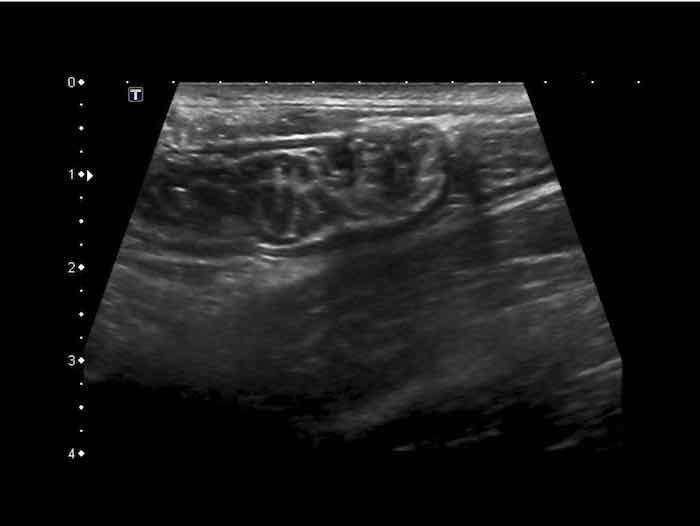

Đo độ dày thành ruột bằng siêu âm là khó khăn vì độ dày thay đổi theo các chuyển động nhu động ruột.

Ở cá nhân này, các số đo trong mặt phẳng dọc (hình trên) và trong mặt phẳng ngang khi ép nhẹ (hình dưới bên trái) có sự biến thiên đáng kể, nhưng khi ép vừa phải (hình dưới bên phải) các số đo có độ tái lập tốt và chính xác.

Vì lớp thanh mạc tăng âm mỏng hiếm khi có thể nhìn thấy rõ, độ dày thành ruột được đo từ bờ ngoài của lớp cơ mặt bụng đến bờ ngoài của lớp cơ mặt lưng, và sau đó tất nhiên, chia đôi.

Thông thường, độ dày thành ruột non đơn lớp khi ép là khoảng 1,5 – 2,5 mm.

Đo độ dày thành ruột bằng siêu âm theo cách này có tính tái lập và tương đương với những gì các phẫu thuật viên thực hiện bằng ngón tay trong quá trình mở bụng để xác định xem ruột non có bất thường hay không.

Ngược lại với hầu hết các quai ruột bệnh lý, các quai ruột non bình thường có thể bị ép xẹp tốt trong thì giãn nghỉ.